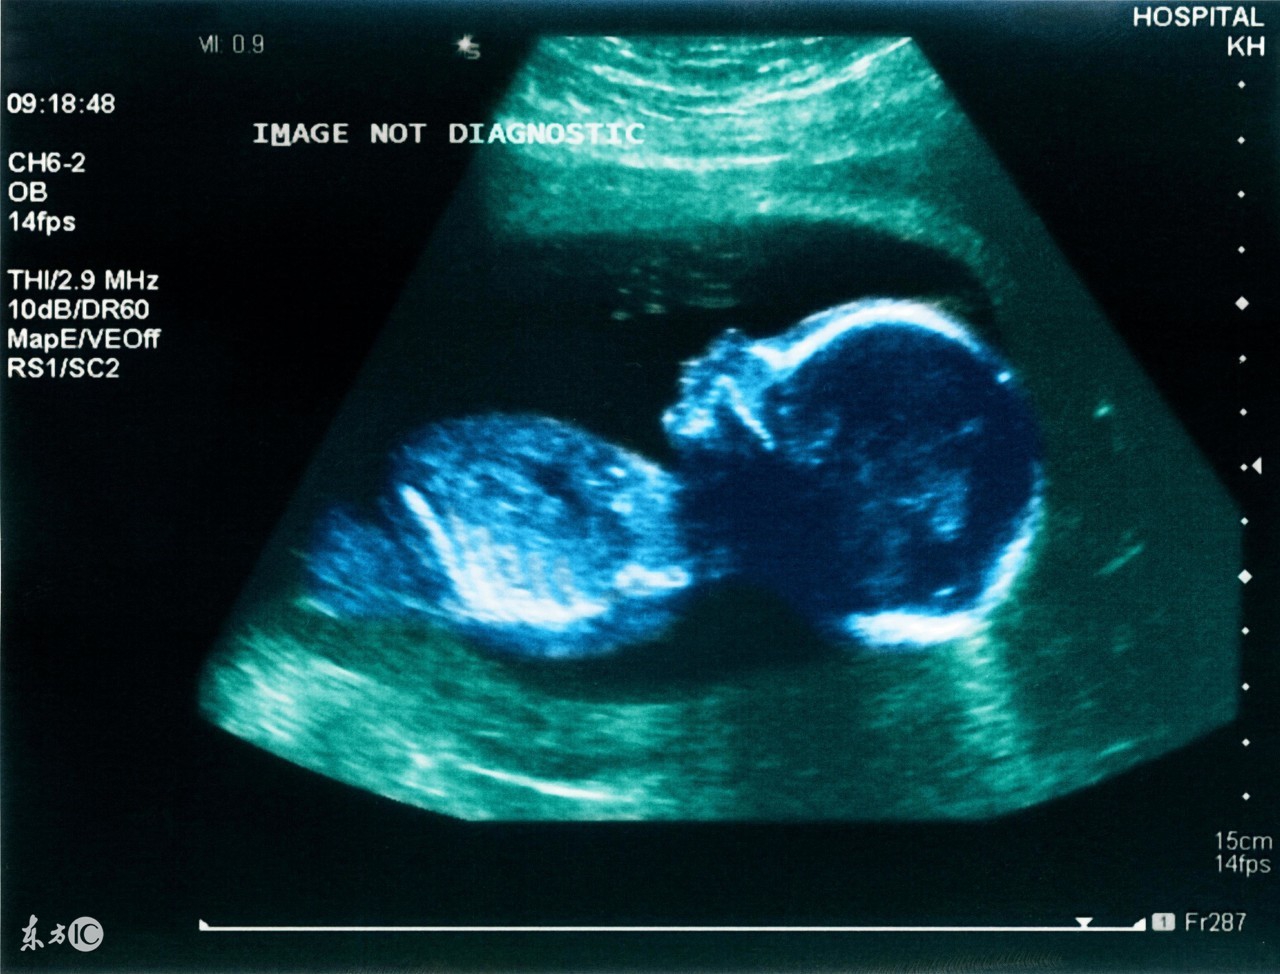

四维彩超是超声检查的一种,除了一般彩超的功能外,还可以进行胎儿头面部立体成像,可清晰地显示眼、鼻、口、下颔等状态,可协助医生直接对胎儿先天畸形进行诊断,包括表面畸形、内脏畸形和头面部畸形,能确定胎儿在子宫中的精确位置。此外,四维彩超还在这些功能的基础上加上时间维度参数,可以实时观察胎儿动态的活动图像。

一般来说,做四维彩超能看出胎儿大方面的畸形,例如新生儿先天性心脏病、唇腭裂、水肿胎、多指(趾)和外耳等方面的畸形均可查出。但四维彩超也不是万能的,例如新生儿耳聋、白内障等就无法检测出来。

四维彩超什么时候做最好?一般来说,怀孕24-28周是照四维彩超的最佳时间,因为胎儿24周左右正是大脑突飞猛进的发育时期,这个时期的胎儿结构已经形成,胎儿的大小以及羊水适中,在宫内的活动空间较大,胎儿骨骼回声影响比较小,图像也比较清晰。